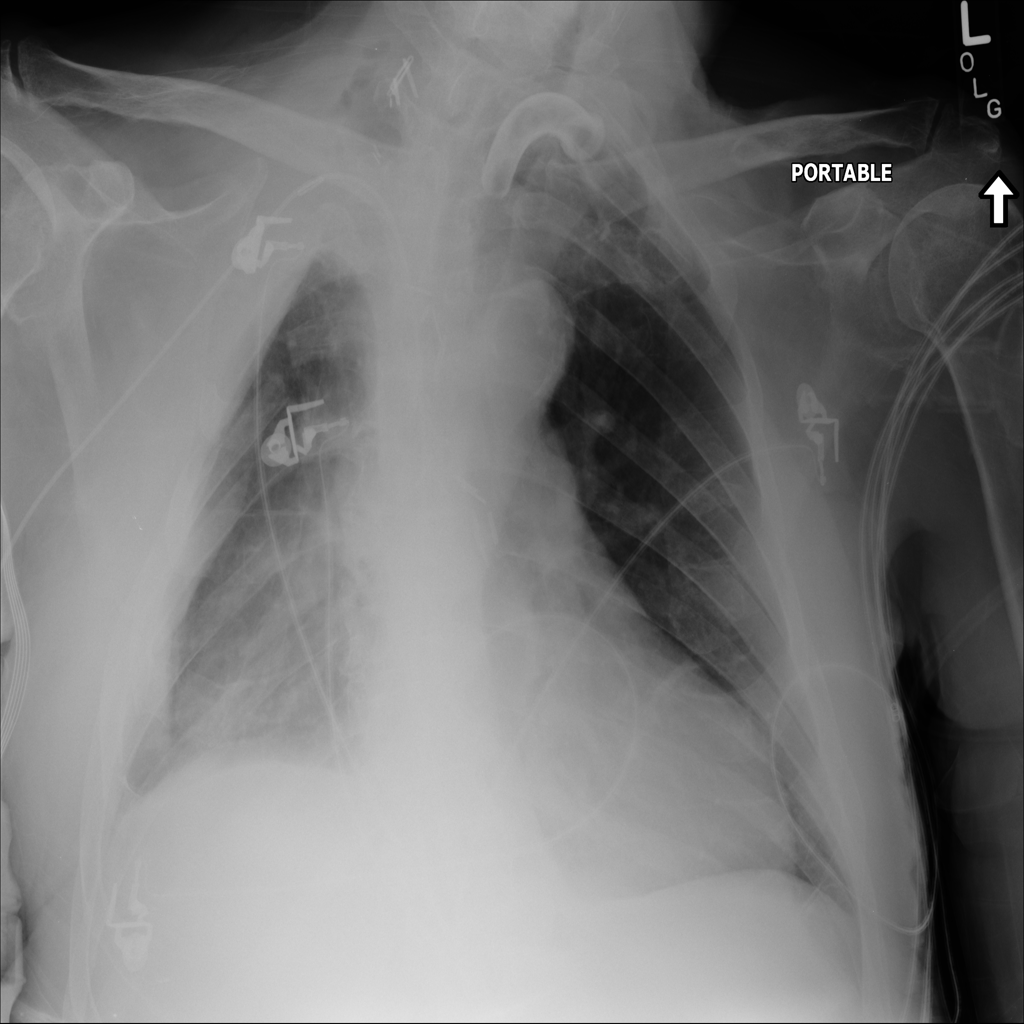

Mass

A mass is a larger focal opacity or lesion seen on the image. It is a descriptive finding that can have several causes and usually needs more imaging or clinical context to characterize.

PAT-290C · IMG-005Mass

PAT-290C · IMG-005

AP